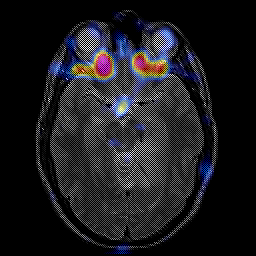

glioma overlay -- Slice #11

[Home][Help][Clinical] Slice 11